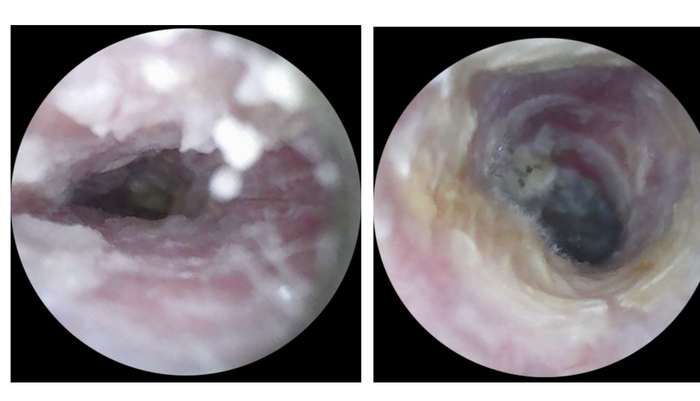

На следующий день «муть» стала расслаиваться. Тоже частый признак именно заброса содержимого носоглотки в ухо.

1/2

Оранжевым оставила границы мутного содержимого, зеленым прозрачного и голубым световой конус.

А на следующий день уши.. поменялись! Теперь первое ухо было отличным, но появилась муть слева. Жалоб также нет, из лечения только промывания и сосудосуживающие на ночь.

Оранжевое - границы мутного содержимого, голубым - световой конус